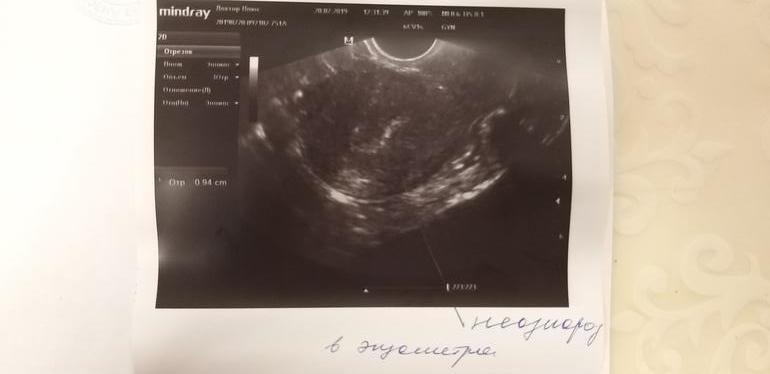

2. Не однородный, не четкий Э, нет трехслойности😭, толщина 9.4 (хоть это радует)